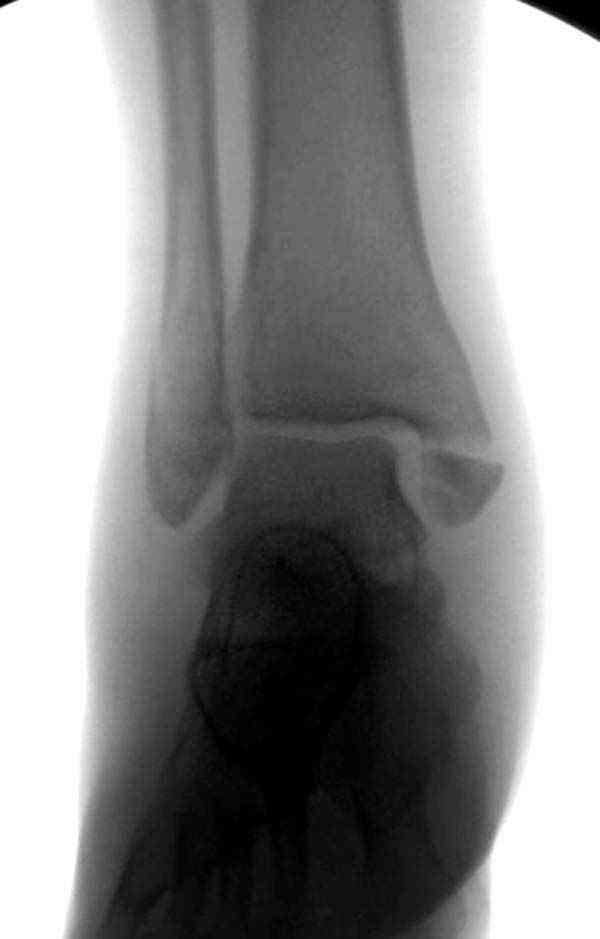

Нет первичных снимков, перелом очень низкий и под большим сомнением диагноз разрыва синдесмоза. Медиальная сторона отрепонирована на "хорошо" и, по-видимому, прорезание проволоки произошло во время операции. Без снимков трудно судить о высоте малоберцовой, а лодыжка находится в варусе. Лагирование получилось, но возле тонких шурупов передне-задний шуруп выглядит немного тяжеловато.

Медиальная лодыжка фиксируется каннюлированными лодыжечными шурупами перкутанно, а неточная репозиция (интерпозиция) является показанием к открытой технике. При больших вертикальных фрагментах нужны противоскользящие медиальные пластины.

Коллеги правы, что при рутинных переломах достаточным бывает обычные снимки с мортизом. А стрессовые рентгенограммы могут уточнить, есть ли разрыв синдесмоза.

Здесь несколько частных случаев: перелом голеностопа со сравнительными снимками и разрыв синдесмоза, а также медиальная Hook пластина.